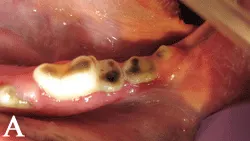

(A) Occlusal view of lower incisors, canines, and premolars. Note the shortened occlusal surfaces with central discoloration. The color change is consistent with reparative dentin formation. Reparative dentin color can range from light tan to reddish-brown to chocolate brown. The surface is typically very smooth. These findings are very common in dogs who favor tennis balls. Over time the abrasive surface of tennis balls will wear away enamel and dentin. If the wear is slow enough and the tooth is still alive, reparative dentin will form. Application of a dentinal sealant is not necessary, since the tooth has already provided its own natural barrier.